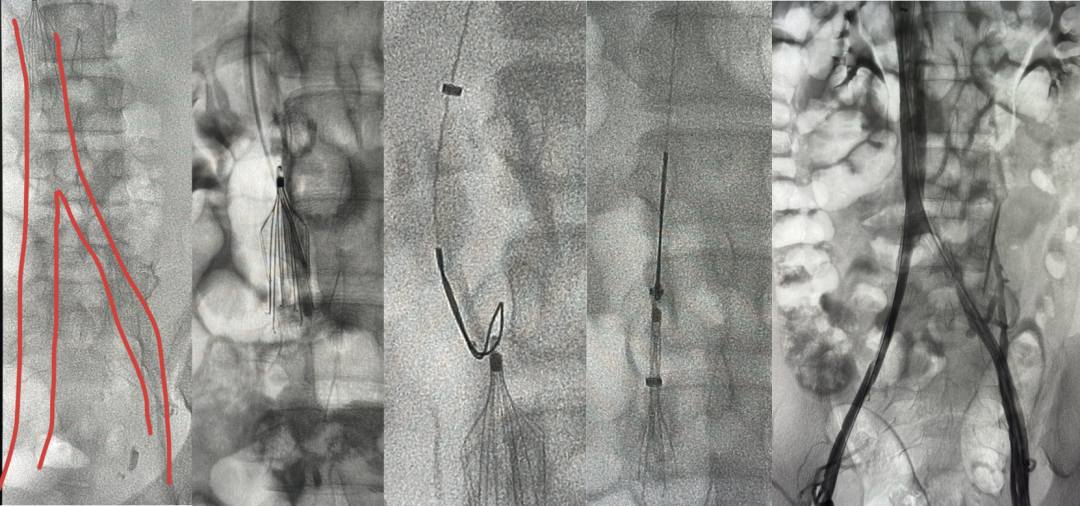

图:不同滤器、不同时期的血栓处理策略

★ Case1:梭形滤器下腔静脉亚急性血栓

图:基线造影情况:右侧股静脉、双髂静脉、下腔静脉血栓性闭塞

图:AngioJet +手动抽吸血栓

图:抽吸后双髂静脉及下腔静脉复通+滤器置换

图:足量抗凝两周后回收临时滤器

图:2年后随访结果

★ Case2:滤器相关慢性血栓闭塞开通后KISS支架